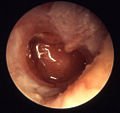

Otitis media with effusion

Otitis media with effusion (OME), also called serous or secretory otitis media (SOM), is simply a collection of fluid that occurs within the middle ear space as a result of the negative pressure produced by altered Eustachian tube function. This can occur purely from a viral URI, with no pain or bacterial infection, or it can precede and/or follow acute bacterial otitis media. Fluid in the middle ear sometimes causes conductive hearing impairment, but only when it interferes with the normal vibration of the eardrum by sound waves. Over weeks and months, middle ear fluid can become very thick and glue-like (thus the name glue ear), which increases the likelihood of its causing conductive hearing impairment. Early-onset OME is associated with feeding while lying down and early entry into group child care, while parental smoking, a short period of breastfeeding and greater amounts of time spent in group child care increased the duration of OME in the first two years of life.[1]